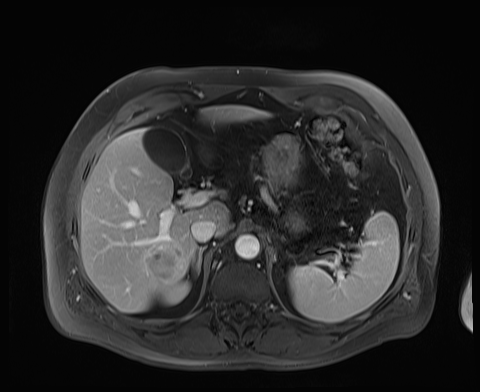

Case 3

20 F with PMH hypoplastic left heart s/p fenestrated Fontan procedure admitted for shortness of breath and hypoxia of uncear etiology.

145/58 mmHg / 78 bpm / 20 breaths/min / 97.6°F / 88% 6L

Faint expiratory wheezing in upper lungs, rhinorrhea, and congestion

AST 33, ALT 33, Alk Phos 222